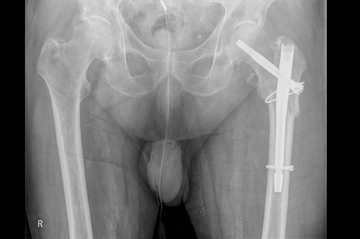

Beckenfrakturen

Beckenfrakturen und Frakturen der Hüftgelenkspfanne (Azetabulum) sind komplizierte, teilweise sogar lebensbedrohende Verletzungen. Schwere, instabile Beckenbrüche treten häufig in Verbindung mit Hochenergieverletzungen wie einem Polytrauma auf. Gefäß- und Nervenverletzungen sind in deren Folge nicht selten und können zu einem massiven Blutverlust führen. Die Erstversorgung hängt von der Schwere der Fraktur und der Begleitverletzungen ab. Bei schweren Verletzungen ist zunächst eine Stabilisierung mit einer Beckenzwinge oder einem Fixateur externe notwendig, um andere Verletzungsfolgen primär zu behandeln.

Zur weiterführenden Diagnostik einer Beckenverletzung steht uns modernste radiologische Bildgebung mit 3D-Rekonstruktion zur Verfügung. Auch intraoperativ ist eine 3D-Bildgebung bei laufender Operation möglich. Zur Therapie von vorderen und hinteren Beckenring-Frakturen favorisieren wir Platten-Osteosynthesen offener Reposition, aber auch minimal-invasive Therapieoptionen und transkutane Verschraubungen.